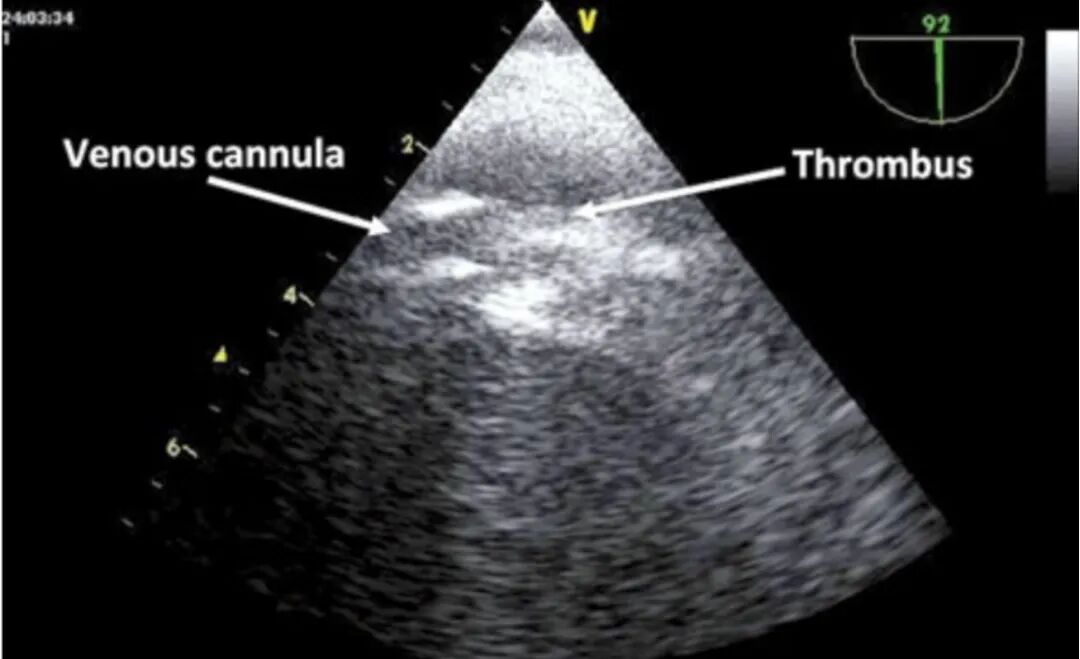

• 导管相关静脉深血栓

一项研究纳入48例V-V ECMO患者,Ca-DVT发生率为85.4%(不同文献报道的发生率有所不同,波动于15%~85%),颈内、股静脉均可形成血栓,不同部位的血栓发生率相当,与抗凝水平无关、与ECMO时长有关。

下图是一例经食道超声证实的静脉血栓,管路的引流端端口存在高回声团块影,考虑静脉引流端血栓。

图片